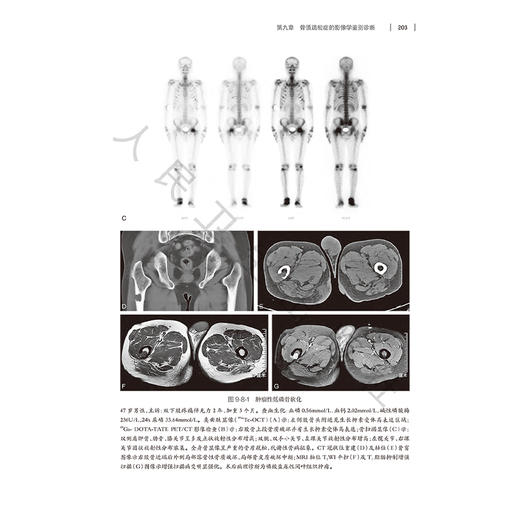

我国已进入老龄化社会,骨质疏松症严重影响老龄人口的健康,骨密度测量和影像学检查在骨质疏松症的诊断和鉴别诊断中发挥重要作用。本书从骨质疏松症的基础、临床入手,详细介绍骨质疏松症的各种影像检查技术,包括X线平片,CT,MRI和核医学在骨质疏松诊断与鉴别诊断中的作用。系统介绍各种骨密度测量方法,重点介绍双能X线吸收法(DXA)、和定量CT(QCT)骨密度测量在骨质疏松症临床诊断、评估中的应用;重点介绍定量CT影像学检查新技术在骨质疏松症诊断和评估中的应用。本书将提高影像科医生、骨科及内分泌等多学科医生对骨质疏松症的诊断和鉴别将发挥重要作用。